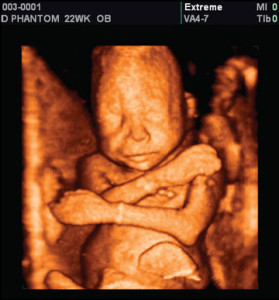

New study shows many premature babies can survive as early as 22 weeks

“Between-Hospital Variation in Treatment and Outcomes in Extremely Preterm Infants” is a study that was published Wednesday in The New England Journal of Medicine. The study found that, while viability is usually set at 24 weeks, babies born as early as 22 weeks may survive if they are treated.

Sadly, a number of hospitals refuse to treat infants who are born before 24 weeks. And yet, this study found that in hospitals that do treat extremely premature infants, they are surviving. In some cases, they are even thriving, with few or no disabilities or effects as they grow older.

This means that, with “active treatment,” babies born at 22 weeks survive at a 23 percent rate. Nearly 40 percent of the survivors did not have serious disabilities, and only 33 percent of them did. Of course, a child who is blind, deaf, or otherwise disabled deserves to live just as a unimpaired child does.

This study is a stunning and important medical accomplishment. Premature babies should be actively saved. The potential for disabilities or a harrowing time spent in NICU should in no way cheat a child out of her chance for life.